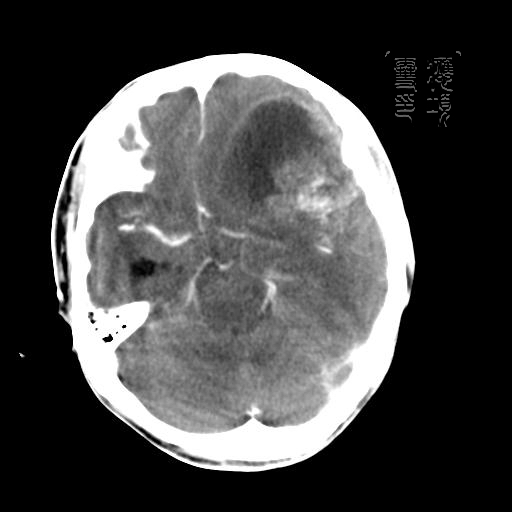

m 52y

二月前癫痫入院, 无既往史,现头痛、呕吐、视力减退、复视行ct平扫及增强检查。

见环形,结节样强化,考虑囊性星型细胞瘤。

考虑囊性星型细胞瘤,ct征象大囊小结节.

左额叶囊实性占位,以囊性为主,并见明显强化不规则壁结节,占位效应明显,首先考虑是囊性星形细胞瘤.

从发病部位及年龄都不考虑是血管母细胞瘤,还有可能是胶质瘤.

环形强化,壁薄、完整、光滑,而且有结节强化,个人考虑不典型脑脓肿多!

胶质母细胞瘤的花边状强化及出血的特点这组片中没体现出来.还是支持囊性星型细胞瘤.